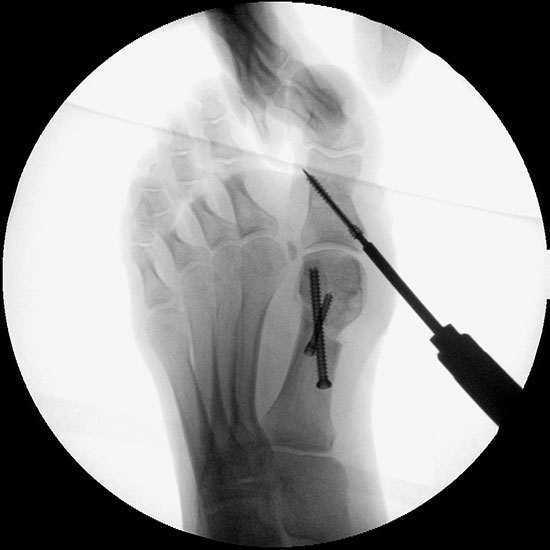

Abbildung 1

• Korrekturpotential größer als beim offenen Chevron, da die Gelenkkapsel als stabilisierendes Element erhalten bleibt und über eine trikortikale Osteosynthese mit zwei kanülierten Schrauben eine Verschiebung bis ca. 80% des Metatarsaledurchmessers möglich ist (Abb. 1).